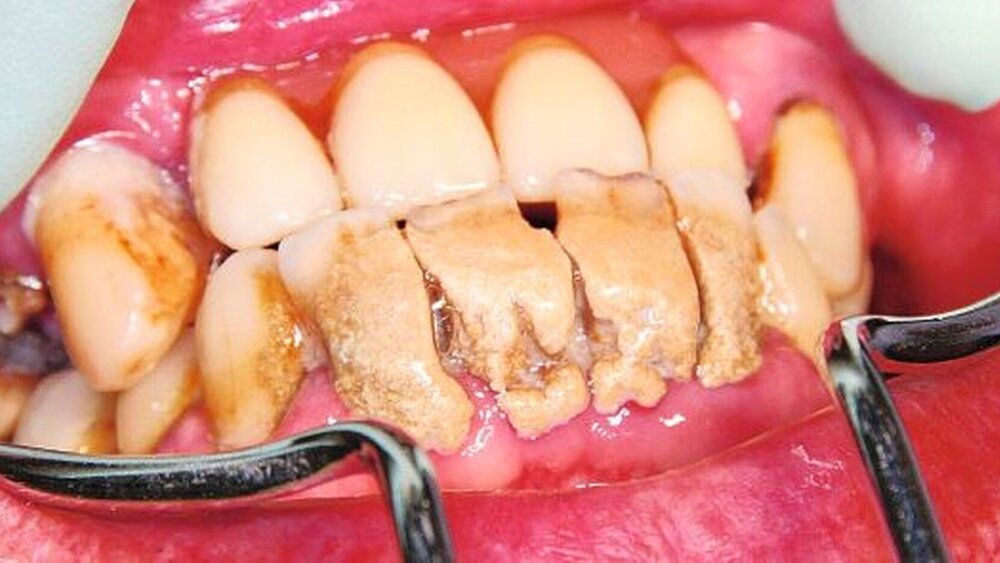

Da reicht eine Notfallbehandlung im Altenheim: Zahnextraktion 26 – der Zahn ist so mit Zahnstein ummantelt, dass er nicht in die Zange passt. Der Patient ist allerdings total glücklich und stolz, dass er die Mundhygiene mit 89 Jahren noch selber durchführt.

Der letzte Besuch dieses Patienten beim Zahnarzt liegt fast 40 Jahre zurück: Der Patient wurde zum 05.01.1970 zur Bundeswehr eingezogen. Da die Zähne im Oberkiefer defekt waren, ließ er sich im Dezember 1969 diesen Zahnersatz anfertigen. Vermutlich ist der Zahnstein ebenso alt.